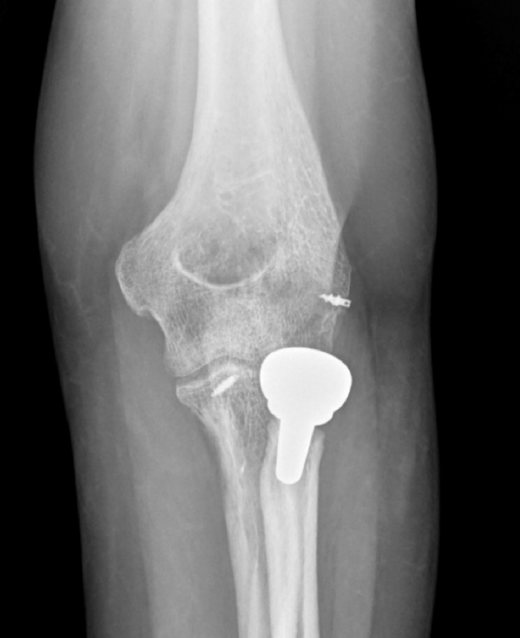

- Tipo I. Las fracturas de la punta de la coronoides son pequeñas y por lo general no son sintetizables. Usaremos un pasador de sutura para llevar una lazada desde el fragmento hasta la cortical posterior del cúbito a través de 2 orificios perforados con broca o bien reinsertaremos la cápsula mediante un arpón(9). Además habrá que tratar el resto de las lesiones cuando se vean involucradas: síntesis o reemplazo de la cabeza del radio, y reinserción o reparación del LCL(10). Si persiste la inestabilidad tendremos que revisar el LCM (Figura 4). Algunos autores han señalado buenos resultados con la reparación o reemplazo de la cabeza radial y reparación del LCL sin fijar la coronoides(11).